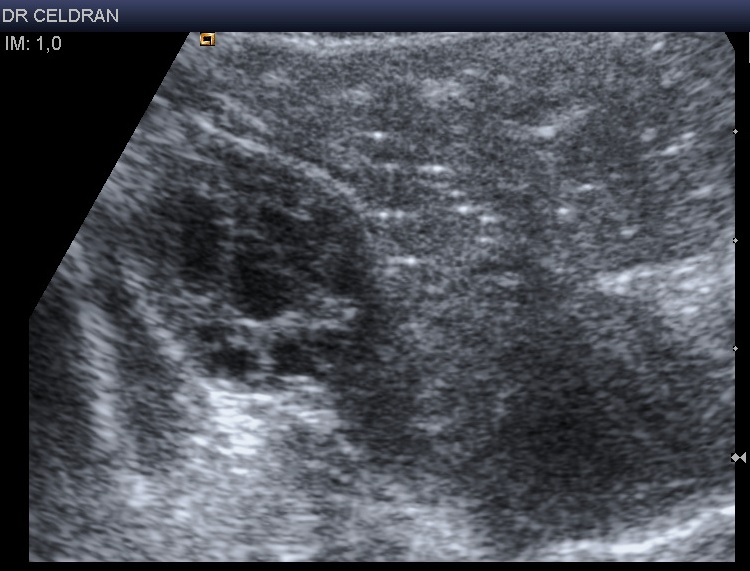

Autre patiente : ovaire droit parfaitement visualisé par voie suspubienne avec une sonde basse fréquence